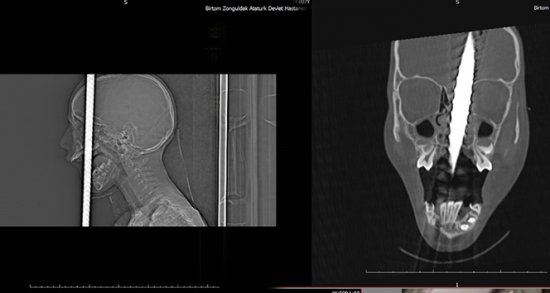

Zonguldak’ta, bisikletiyle gezerken 2 metre yükseklikten düşen 7 yaşındaki Fırat Başaran’ın ağzından giren demir başından çıktı. Yaralı çocuk, ekipler tarafından Bülent Ecevit Üniversitesi Uygulama ve Araştırma Merkezine sevk edildi. Beyin cerrahisi, kulak burun boğaz, plastik cerrahisi, anestezi ve AFAD ekipleri başarılı bir ekip çalışması sonucunda 6 saat süren operasyonla 1 metre uzunluğundaki demir çubuk operasyonla alındı. Çocuk yoğun bakım ünitesine kaldırılan 7 yaşındaki Fırat Başaran’ın tedavisi devam ediyor.

İlk günlerin büyük önem taşıdığını ifade eden Beyin ve Sinir Cerrahisi Anabilim Dalı uzmanı Doç.Dr. Şanser Gül ise, “Hastamızı ilk olarak Atatürk Devlet Hastanesinde beyin cerrahisi uzmanı operatör Dr. Emrah Keskin görüyor ve durumu bize haber veriyor. Biz hazırlığımızı yaptık. Temel prensip ilk önce zarar vermeme, üst damaktan ağız içinden giren ve yaklaşık 1 metre uzunluğundaki demir çubuk kafatasını delerek sol ön fontelden 40 santim dışarı çıkmıştı. AFAD ekipleri tarafından 3 santim kalana kadar kesildi. Temel prensiplere bağlı kalarak parçalanan bölgeyi genişleterek demir çubuk rahatlatıldı. Sonra ameliyata alınarak demir çubuk çıkartıldı. Ön beyin düşünce davranışlarımızı yönlendirir; hafıza, düşünme, karar verme, idare etme gibi durumları evet çocuğumuz şu an yoğun bakımda bilinci açık bir şekilde zaman içinde neyi kaybettiğini görmüş olacağız. İlk günlerde hayati önem taşıyan bir durum var o da enfeksiyon ekip olarak tüm işlemler yapıldı. Antibiyotik tedavisine başlandı. İlerleyen günler her türlü sonuca açık” şeklinde konuştu.